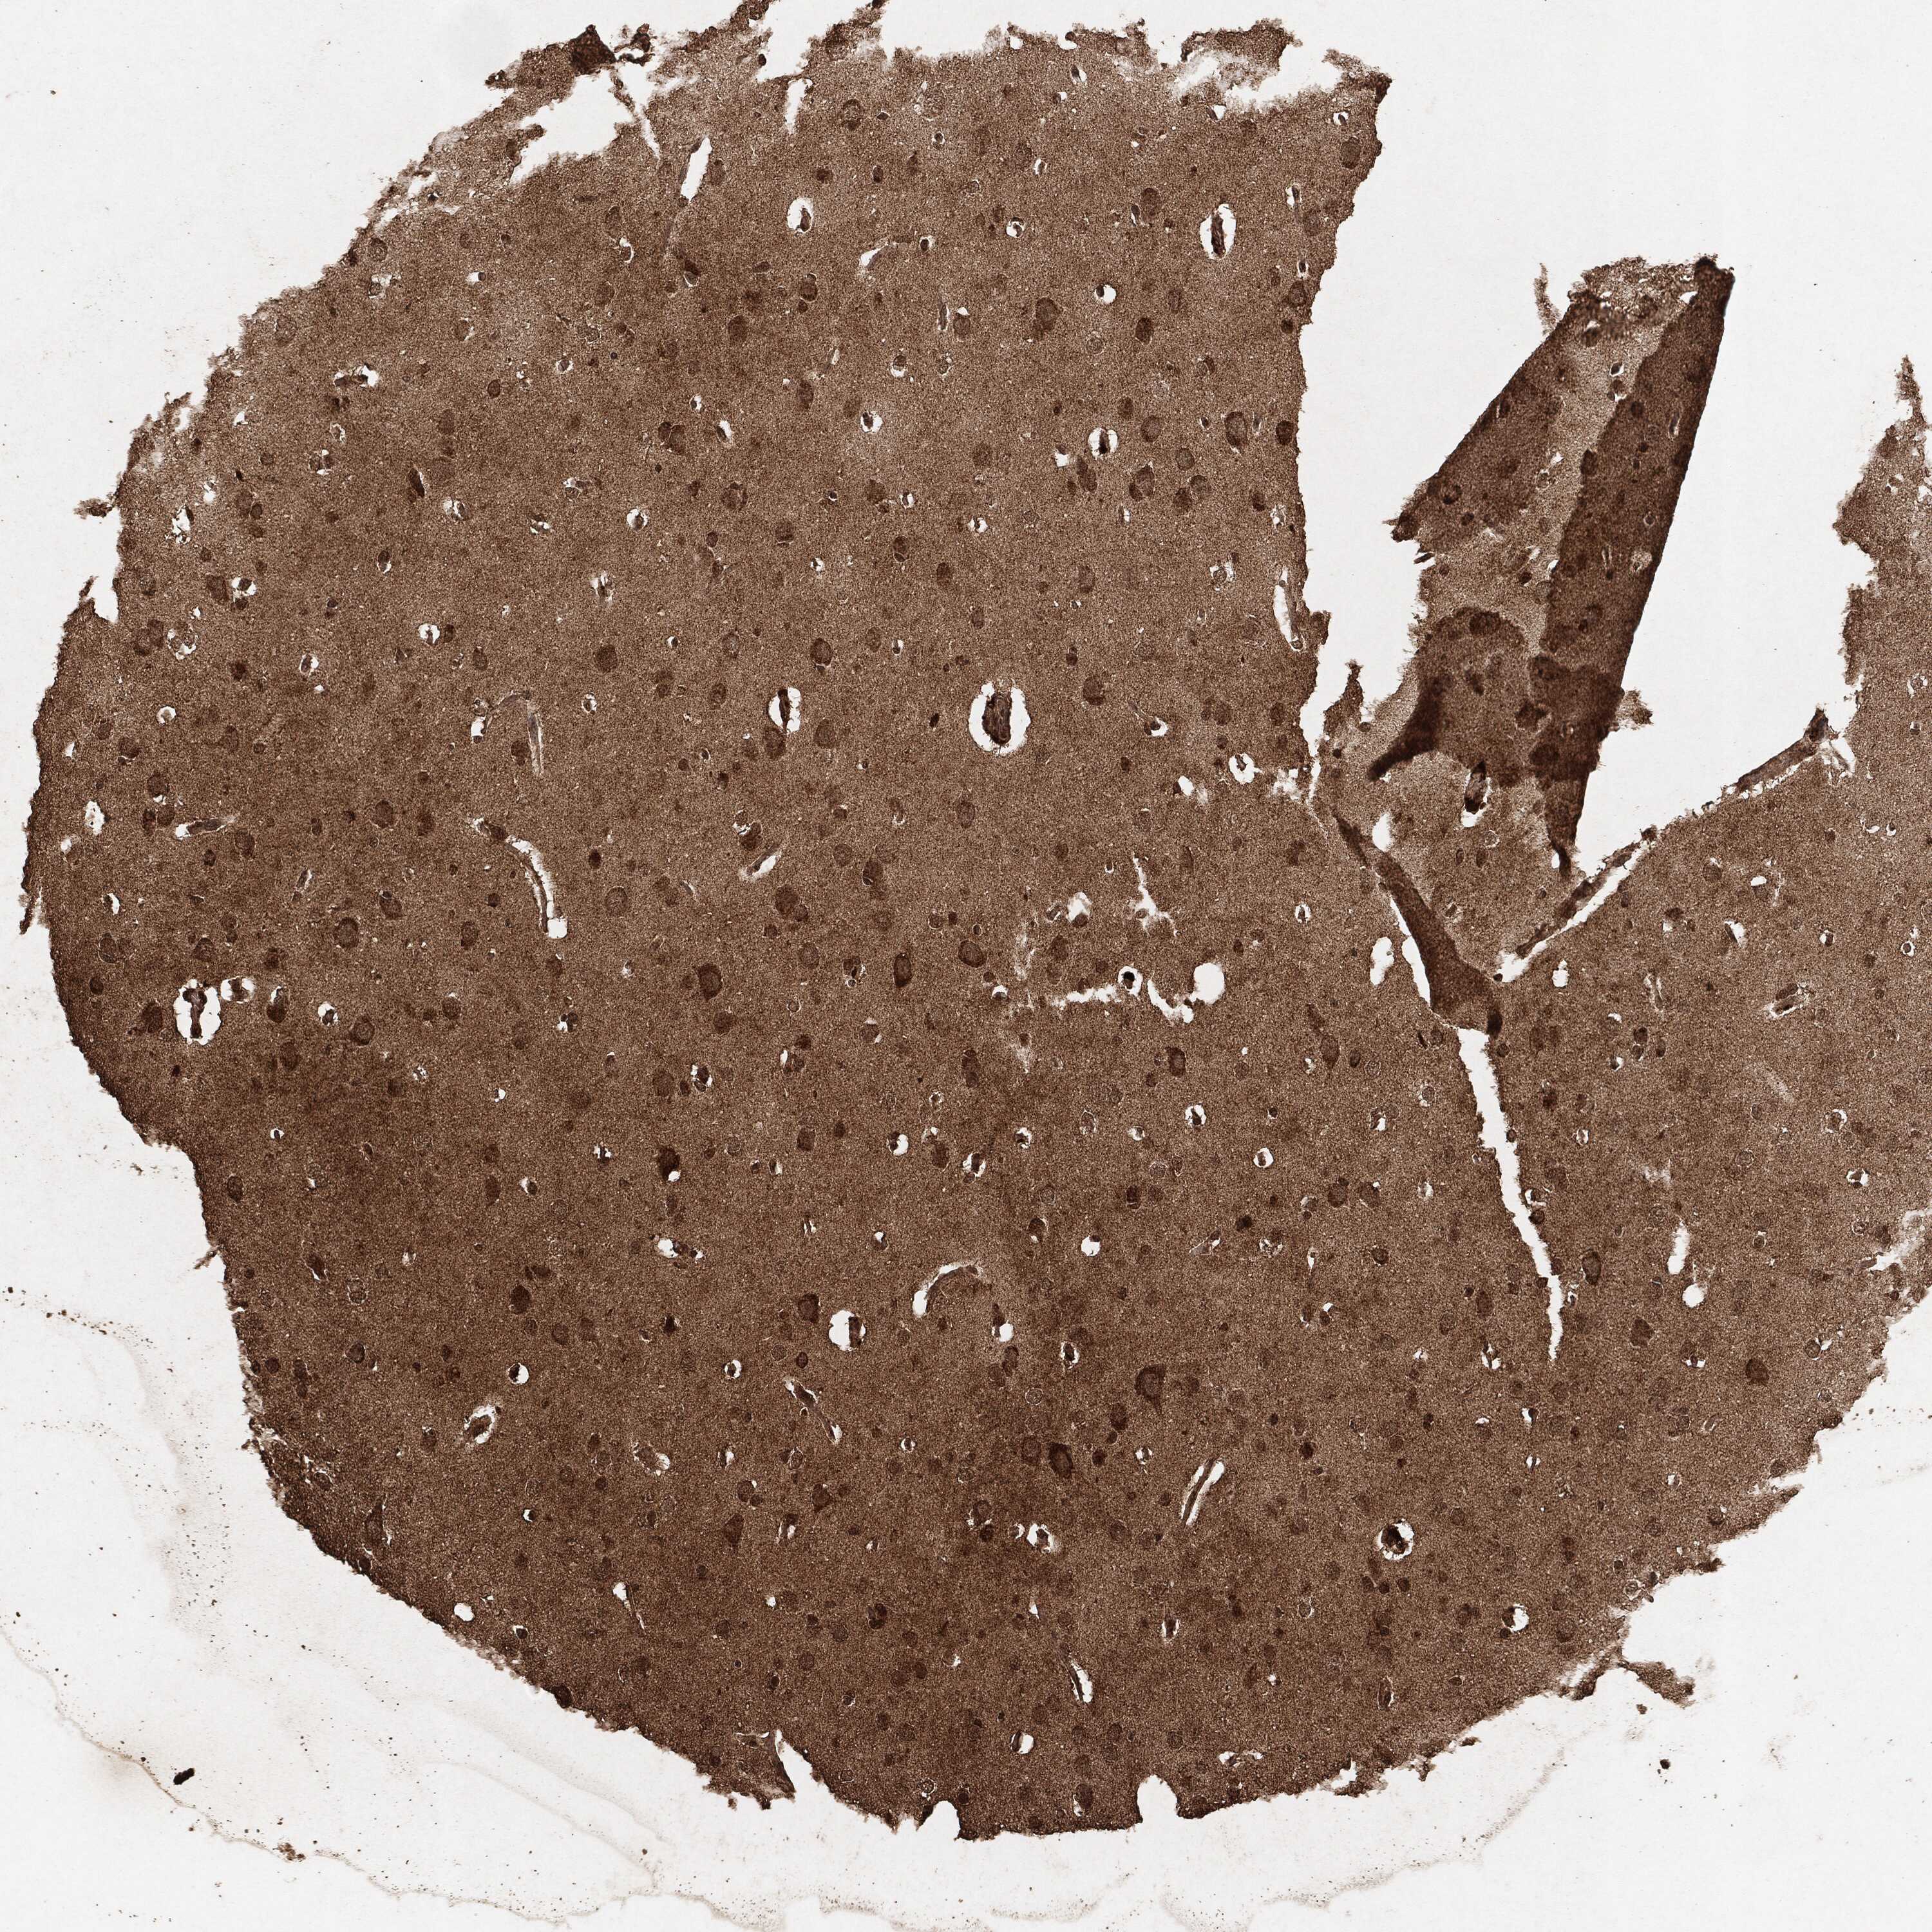

GLIOMA - Protein expressioni

A mouse-over function shows sample information and annotation data. Click on an image to view it in a full screen mode. Samples can be filtered based on level of antibody staining by selecting one or several of the following categories: high, medium, low and not detected. The assay and annotation is described here.

Note that samples used for immunohistochemistry by the Human Protein Atlas do not correspond to samples in the TCGA dataset.

Antibody stainingi

Antibody staining in the annotated cell types in the current human tissue is reported as not detected, low, medium, or high, based on conventional immunohistochemistry profiling in selected tissues. This score is based on the combination of the staining intensity and fraction of stained cells.

Each image is clickable and will lead to virtual microscopy that enables deeper exploration of all samples and also displays staining intensity scores, fraction scores and subcellular localization as well as patient and tissue information for each sample.

Glioma, malignant, High grade

Glioma, malignant, Low grade

Glioma, malignant, NOS